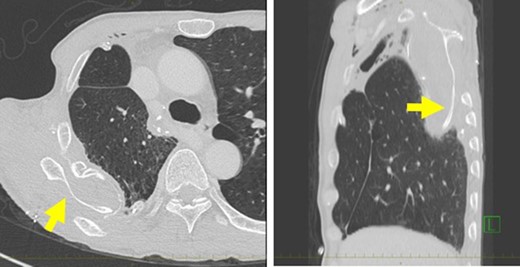

Postoperative acute course was uneventful. However, at postoperative Day 6, he experienced acute severe pain in the right shoulder. The slightly purulent drainage through drainage tube positioned on the mesh was also found. Pus culture from the drain discharge isolated Corynebacterium atrium. Computed tomography (CT) revealed that when the symptoms appeared, abnormal position of the right scapula with the inferior angle of the scapula was caught inside the top of the sixth rib (Fig. 1). The conservative treatment failed to improve the scapular dislocation. We performed a redo surgery. We found that all suture threads which attached Mesh to sixth rib were cut, and the dislocation of the right scapula with the inferior angle of the scapula protruding into the right intrathoracic cavity though his thoracotomy defect (Fig. 2). We also found a local infectious change at the head side of the Mesh (not the site of scapular dislocation), and found no macroscopic intrathoracic infectious changes. A removal of mesh was carried out. After improving the scapular dislocation and removal of mash, washing with 10 L of physiologic saline was carried out. We did not want to use synthetic materials because of infection. In this case, however, the infection was localized and titanium plate is reported to be resistance to infection [8], we performed titanium plate fifth rib fixation to avoid the recurrent dislocation of the scapula (Fig. 3). After the redo surgery, continuous lavages with physiologic saline of the thoracic cavity and antibiotic therapies were also performed for 21 days. The repeated culture of the drainage showed no bacterial isolation. After removal of drainage tube, there was no recurrence of infection and scapular dislocation. He had full range of motion of his right shoulder without pain. Patient is now doing well with free from recurrences of cancer, infection and scapular dislocation, 16 months after the redo surgery.

(A) Computed tomography (CT) demonstrating a dislocation of the right scapula in the right thoracic cavity. (B) Sagittal reconstruction of the CT also showed the dislocation of the right scapula.